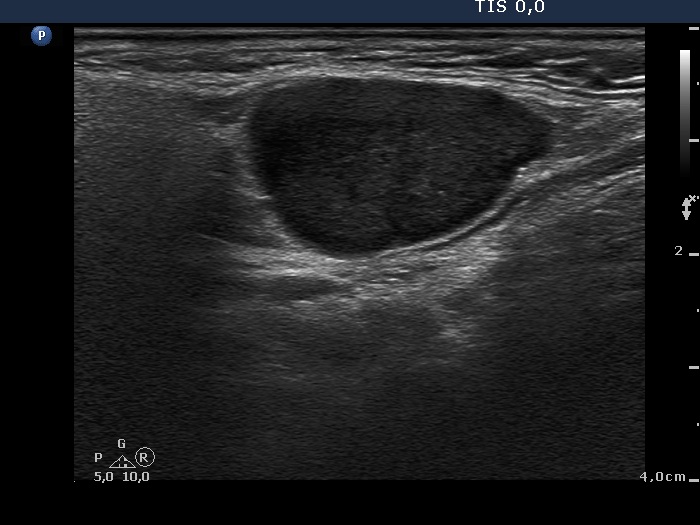

Lymph nodes in the neck - Case 1160 (ultrasonographic picture 5)

Right submandibular area, longitudinal scan.